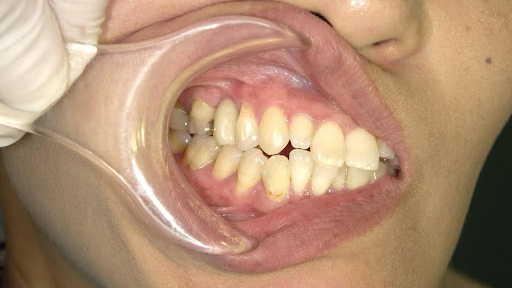

Before

枚方市のインプラントの症例

T・T 様 女性 40代

症状としては、 右上5番の歯が折れてしまった。保存することは不可能な状態であった

治療法としては、患者様は、歯が折れたことを主訴に来院。インプラント治療を希望したため、抜歯した当日に、インプラント埋入をおこなって、骨欠損部には人工骨を補填した。1か月半後にインプラントが骨と結合していることを確認できたため、光学印象を行い、2か月後に、最終補綴物として、アバットメントとジルコニアクラウンの装着を行いました。

治療結果としては、抜歯したと同時にインプラントを埋入することで、抜歯した穴が自然に治る過程で、インプラントの骨結合と組織の治癒が同時に行われるために、2か月という治療期間で治療を終了することができたことと、機能面・審美面でも回復を行うができた。

治療の期間・回数:約2か月、インプラント抜歯即時埋入から最終補綴物装着まで4回

治療の価格:352,000円(税込)

治療費の内訳:インプラント基本料(フィックスチャー及び手術費用、投薬費用、レントゲン費用、インプラント上部費用(アバットメントおよびジルコニアクラウンの費用用)330000円(税込み)。オプション、抜歯即時埋入加算(人工骨費用を含む) 22000円(税込み)

治療のリスクや副作用:手術後に、痛みや腫れ、出血、合併症などを引き起こす可能性があります。噛む感覚がご自身の歯と異なる場合があります。見た目がご自身の歯と異なる場合があります。手術後にメインテナンスを継続しないと、インプラントが抜け落ちる可能性があります。